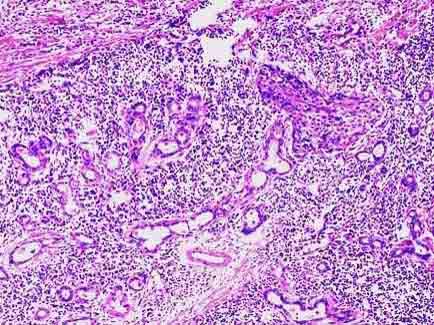

问题 患者男性,58岁,进行性声嘶2月,伴吞咽困难,临床检查示喉部新生物。活检镜下如图,正确的诊断是 ( )

选项 A.喉乳头状瘤 B.喉恶性淋巴瘤侵及固有腺体 C.喉低分化鳞状细胞癌侵及固有腺体 D.喉腺癌 E.喉高分化鳞状细胞癌侵及固有腺体

答案 C